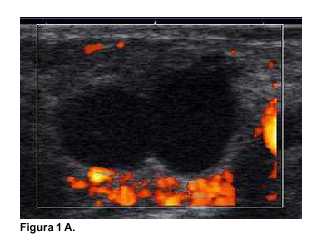

En todas las pacientes la neovascularización se objetivó precozmente mediante la ecografía. En las imágenes obtenidas (figuras 1A, 2A y 3A), se observan como zonas coloreadas en rojo y naranja. Desde el punto de vista endocrino la evolución se presenta en las gráficas contenidas en las figuras (figura 1B: caso 1, figura 2B: caso 2, y figura 3B: caso 3). Se destaca que todas las pacientes presentaban valores normales de E2 y FSH en el preoperatorio.

El primer caso clínico (figura 1) presentó valores de castración (FSH alta y E2 bajo) en el primer mes posoperatorio, al segundo mes se elevó el E2 persistiendo alta la FSH. Al cuarto mes se recuperó el patrón normal de FSH y E2. Es en ese momento que mediante ecografía se reconocieron cuatro folículos en maduración en el implante subcutáneo.

En estos tres casos fue posible sacar conclusiones de los autoinjertos de corteza ovárica a mediano plazo. A diferencia del caso publicado recientemente por nuestro grupo, en el que se mantuvo un ovario intraabdominal translocado(13), en estos casos la evolución depende exclusivamente de los injertos heterotópicos. La ecografía Power Doppler evidencia la enorme capacidad de neo-vascularización que tiene el tejido ovárico. Se trata de un evento precoz, que ya puede observarse dentro de la primera semana. Desde el punto de vista endocrinológico las pacientes, partiendo de una función normal, y luego de operadas, atraviesan un período de "castración" con una FSH muy elevada, 50 mU/ml (paciente 1), 100 mU/ml (paciente 2) y 110 mU/ml (paciente 3), con E2 muy bajo (menor de 10 pg/ml en todas). El primer signo de recuperación es un ascenso del E2 sanguíneo que ocurre al segundo mes en la paciente 1, al cuarto mes en la paciente 2, y al tercer mes en la paciente 3. Finalmente, se produce un descenso de la FSH a valores próximos a la normalidad. La reducción de la FSH está señalando la reestructuración de la granulosa folicular capaz de secretar inhibina, que realiza un "feed back" negativo a nivel hipofisiario con la FSH. En las tres se desarrollaron folículos en maduración, que coincidió con la normalización del estradiol.